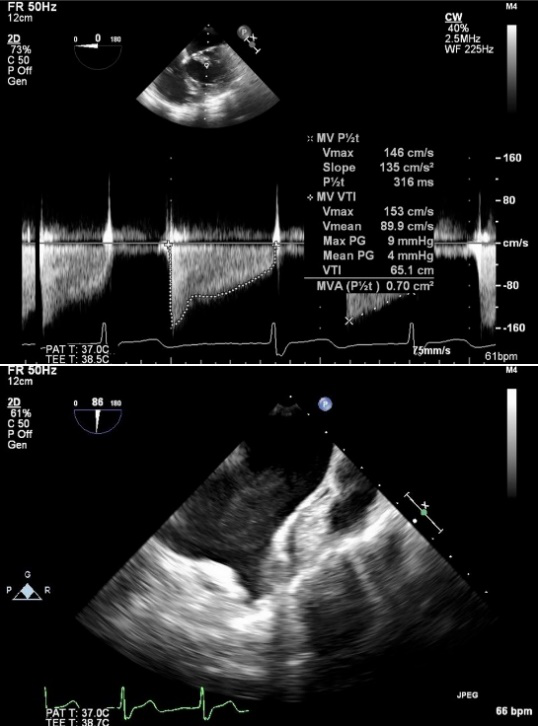

患者华法林抗凝治疗3年,INR达标情况下左房血栓仍存在,就诊于多家医院均无有效治疗手段,遂就诊于中山医院。我院食道心超提示重度二尖瓣狭窄、左房内附壁血栓形成、中度肺高压(图1)

图1. 术前食道心超

沿动静脉轨道送INOUS二尖瓣扩张球囊至二尖瓣口,依次以18mm、19mm、20mm、22mm扩张(图4),术后心超测得二尖瓣瓣口面积2.2cm2,彩色多普勒示轻微二尖瓣反流(图5)

图5. 扩张后食道心超